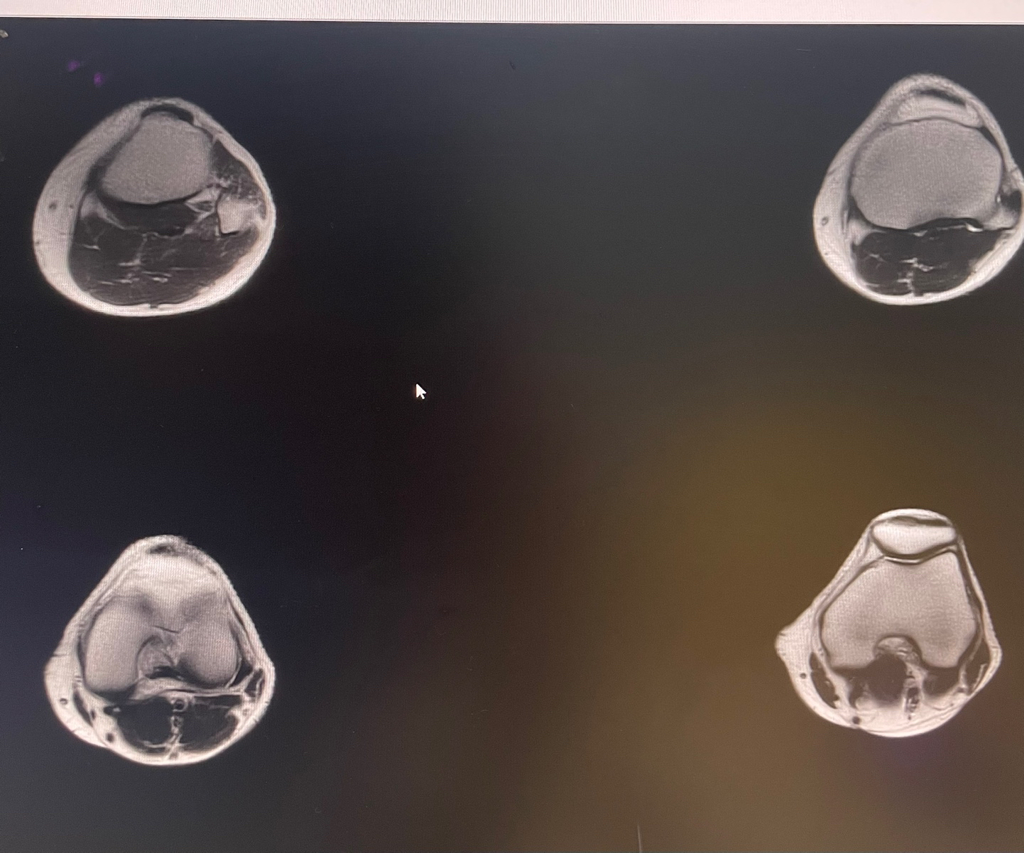

무릎 mri 원형원골인지 봐주실 수 있을까요

무릎이 너무 자주 아파서 mri를 찍어봤는데 무릎 연골에 이상이 있을까요

무릎이 선천적으로 원형연골인지 봐주시면 감사하겠습니다

• 1번 째 사진

• 2번 째 사진

MRI 판독에는 퇴행성 연골 손상, 바깥쪽 원판형 반월상 연골 이 의심된다고 적혀 있습니다.